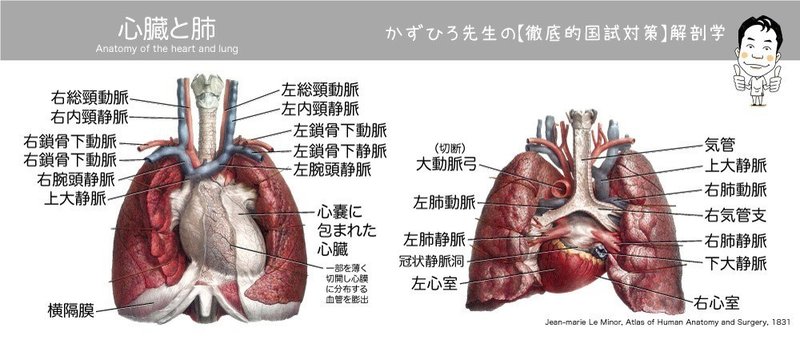

心臓の中の構造 弁や心房・心室の位置を解説 では続いて、心臓の中がどうなっているのか、確認してみましょう。 胸郭を除いたこの図では内胸動脈も図示されていません。 もちろん日頃の予防も大事 心臓病はとても重大な疾患です。

心臓の中の構造 弁や心房・心室の位置を解説 では続いて、心臓の中がどうなっているのか、確認してみましょう。 胸郭を除いたこの図では内胸動脈も図示されていません。 もちろん日頃の予防も大事 心臓病はとても重大な疾患です。

右心房と右心室の間にあるのが三尖弁【さんせんべん】、右心室と肺動脈の間にあるのが肺動脈弁【はいどうみゃくべん】、左心房と左心室の間にあるのが僧帽弁【そうぼうべん】、左心室と大動脈の間にあるのが大動脈弁【だいどうみゃくべん】です。 右の境界は,胸骨右縁から 2 cm 外側で,第 3 胸肋関節から第 6 胸肋関節関節までです。

心房の筋層は心室に比べて厚い 心臓の前面• さらに心臓は心膜に包まれ、心臓との間に心膜腔(心嚢)と呼ばれる間隙があります。 『本当に大切なことが1冊でわかる循環器』より転載。 このような心臓全体としてのリズミカルな拍動は、前述した刺激伝導系によってもたらされる。